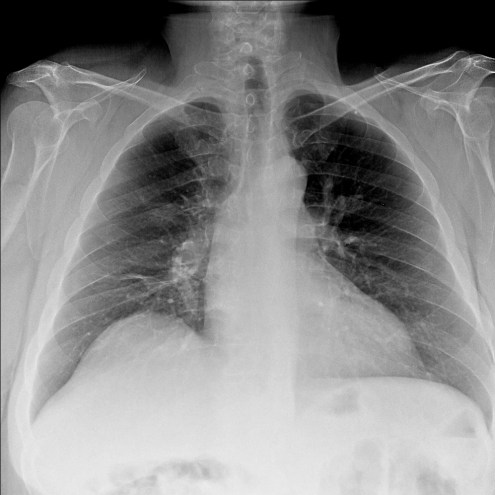

Empecemos, ¿qué ves?

- Comprobar que la placa está bien centrada e inspirada (6 arcos costales anteriores ó 9 posteriores).

- Abdomen y Diafragma

- Partes blandas y estructura ósea.

- Mediastino con silueta cardiaca.

- Parénquimas pulmonares (por separado)

- Comparar un pulmón con otro.

Seguir esta sistemática, dejando el pulmón para el final no nos olvidaremos de lo más importante.

Regla: Acaso Tiene Mucha Patología Pulmonar (Abdomen, Tejidos blandos y hueso, Mediastino, Pulmón por separado, Pulmón bilateral)

Nota: ¡¡¡No olvidar la placa lateral!!! La regla a seguir es la misma. Leer abdomen y diafragma, examinar parte posterior, tejidos blandos y subir por la columna; tráquea y descender por mediastino. Finalmente pulmones.

Solución: Es un estudio Normal. Silueta cardiomediastínica y parénquimas pulmonares sin alteraciones significativas.